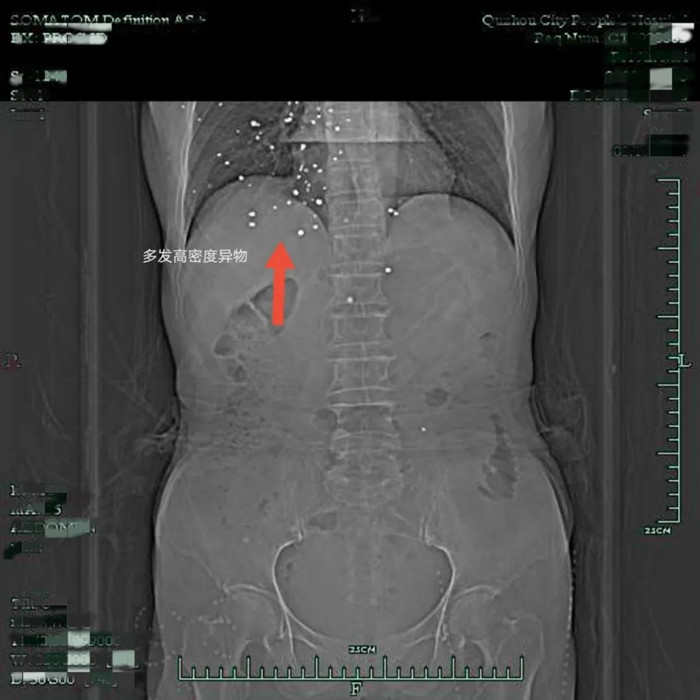

原以為這是一次普通的胃癌手術(shù),沒想到裴阿姨入院后的胸部CT檢查結(jié)果,讓人大吃一驚——在裴阿姨右側(cè)胸廓皮下軟組織內(nèi)、右肺、右側(cè)心包膜下、兩側(cè)心膈角區(qū)有散在結(jié)節(jié)狀致密影。

片子上這一顆顆密密麻麻的小白點是什么?

影像學(xué)上,這種密度高度懷疑是金屬滯留,為什么在裴阿姨的體內(nèi)有多發(fā)金屬?

原來,裴阿姨曾在多年前遭遇過一次意外,導(dǎo)致散彈傷,而這次意外則給她后續(xù)的治療帶來了不小的難度。